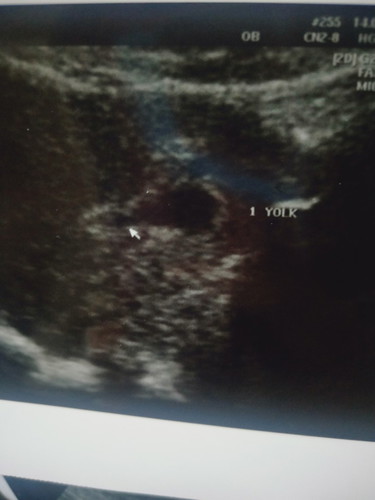

ขอดูภาพ 7 สัปดาห์ของแม่ๆๆหน่อยค่า ส่วนของเราเป็นแบบนี้...หมอบอกว่าเห็นหัวกับหาง ส่วนตัวยังไม่ค่อยชัดเท่าไหร่

ซาวด์ผ่านช่องคลอดตอน7w ค่ะ ปัจจุบันคลอดแล้วน้องอายุ4เดือนแล้วค่ะ 7wยังดูไม่ออกหรอกค่ะว่าส่วนไหนเป็นส่วนไหนเพราะน้องเล็กเท่าเม็ดถั่วอยู่เลย